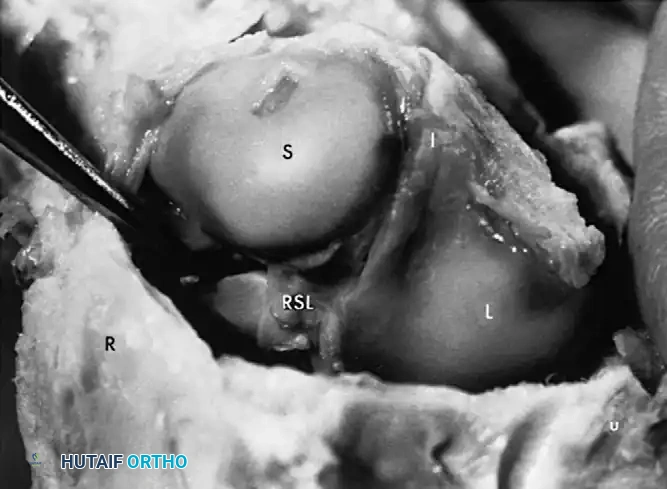

Fig. 66-76 Radioscaphoid ligament (RSL) and surrounding capsular anatomy.

Scapholunate (SL) dissociation is the most common and clinically significant carpal instability. It results from injuries to the dorsal and volar portions of the scapholunate interosseous ligament, the long radiolunate ligament, and the radioscaphocapitate ligament.